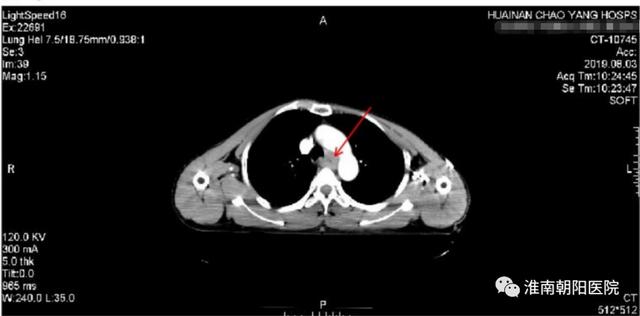

近年来,淮南朝阳医院肿瘤中心努力学习先进医疗技术,经过仔细会诊讨论,为张大爷制定了「免疫治疗+分子靶向治疗+化疗」三种联合综合治疗方案。3 月 26 日「阿帕替尼+卡瑞利珠单抗+卡培他滨」三种药物联合治疗开始。经过 3 个多月 4 疗程的治疗,张大爷身体状况好转,进食不畅、恶心、纳差的症状基本上都消失了,体重也增加了 10 斤。

7 月初我们复查时惊喜地发现两肺多发转移灶和右侧胸廓入口处淋巴结明显缩小。

上图是张大爷免疫综合治疗后的 CT,可以看见以前的转移灶基本消失了